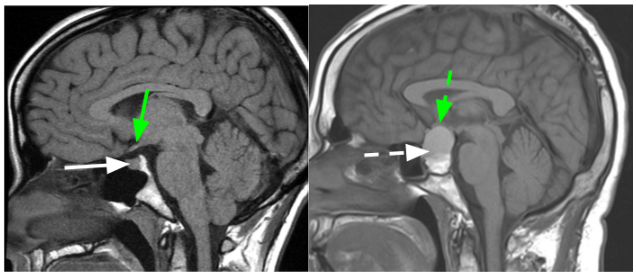

Hipofiz Adenomları

Hipofiz adenomu, hipofiz bezinde oluşan bir tümördür. Bu tümör, hipofizin ön bölgesinde yer aldığından endokrin sistemin düzenlenmesinde önemli bir rol oynar. Hipofiz adenomları genellikle iyi huylu olup, çoğu zaman belirti vermezler. Bununla birlikte, bazı adenomlar büyüyebilir ve komşu dokulara baskı yaparak baş ağrısı, görme değişiklikleri, hormonal dengesizlikler gibi semptomlara neden olabilir.

Hipofiz adenomu tedavisi, tümörün büyüklüğüne, semptomların şiddetine ve hormon düzeylerine bağlı olarak belirlenir. Genellikle, küçük boyutlu ve semptomsuz olan adenomlar izlem altında tutulabilir. Ancak büyüklükleri veya semptomlara neden olmaları durumunda cerrahi müdahale gerekebilir.

Cerrahi tedavi genellikle transsfenoidal cerrahi olarak adlandırılan bir yöntemle gerçekleştirilir. Bu prosedürde, burun yoluyla sinüs boşluklarına ulaşılır ve tümör çıkarılır. Cerrahi müdahale sonrasında, hastanın hormonal düzenlemeyi sürdürebilmesi için bazen hipofiz hormonlarını takviye etmek gerekebilir.